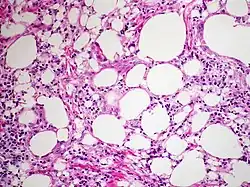

The gross appearance of a lipoid pneumonia changes during different stages of the disease. The lung can appear gray, yellow, or gray-white and may exude oil or form nodules or cavities.[3]

At the microscopic scale, lipoid pneumonia is characterized by abundant foamy macrophages and giant cells. There may also be lipoid vacuoles, and cholesterol clefts.[3] If necrosis is present, there is likely an infection such as secondary tuberculosis.[3]